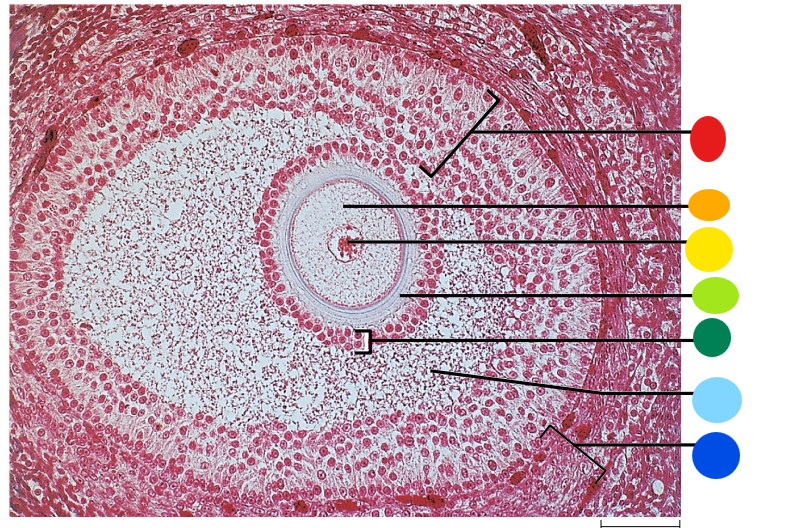

red

granulosa cells

orange

primary or secondary oocyte

yellow

oocyte nucleus

light green

zona pellucida

dark green

cumulus oophorus

light blue

antrum

dark blue

thecal cells

what is this

tertiary follicle